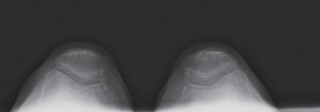

2. التصوير بالأشعة السينية (X-ray):

تُعد الأشعة السينية هي الأداة التشخيصية الأساسية لتقييم خشونة الركبة. يلتقط الأستاذ الدكتور هطيف صورًا للركبة من زوايا مختلفة، بما في ذلك صور الوقوف (Weight-bearing X-rays)، والتي تُظهر المفصل تحت تأثير وزن الجسم الطبيعي. تُظهر الأشعة السينية ما يلي:

- تضييق المسافة المفصلية: خاصة في الجانب الإنسي للركبة، مما يشير إلى تآكل الغضروف.

- تكون النتوءات العظمية (Osteophytes): وهي نتوءات عظمية صغيرة تتشكل حول حواف المفصل نتيجة للتآكل.

- تغيرات في كثافة العظام: مثل التصلب تحت الغضروفي (Subchondral Sclerosis).

- درجة الانحراف التقوسي: قياس الزوايا المحورية للساق لتحديد مدى التقوس بدقة.